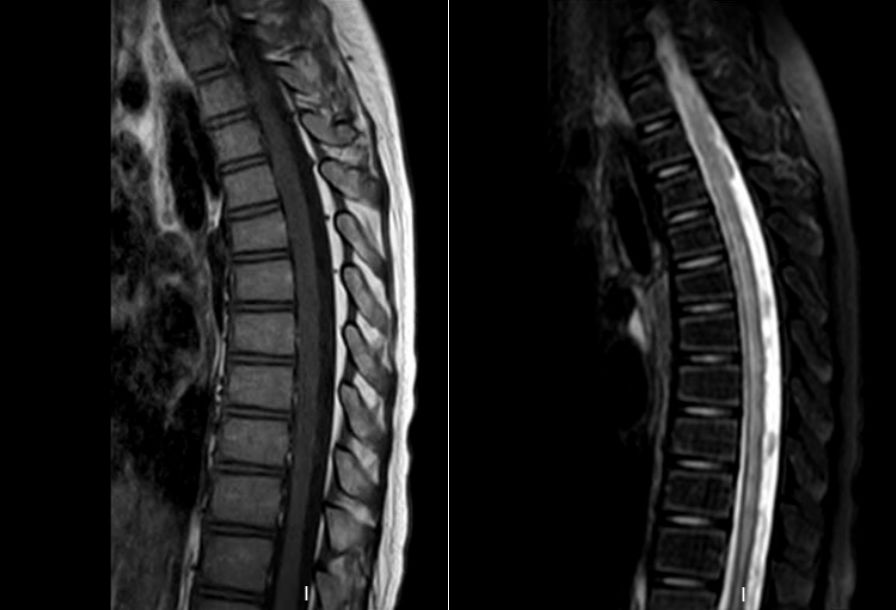

头颅MR:左侧小脑半球异常信号,左侧脑室体部后外侧异常信号,双侧半卵圆中心、侧脑室旁血管周围间隙增多。颈胸髓及腰骶部MRI提示:C3-T4平面脊髓肿胀,伴多发异常信号,胸髓全段肿胀,伴信号异常,腰骶髓异常信号影,考虑脊髓炎可能(图1)。

再次入院后予完善相关检查,相关病毒检测均提示阴性,炎症指标不明显。请神经外科会诊:结合患儿有下肢乏力,行走不稳,腰背部及双下肢疼痛,小便困难,大便失禁及便秘等症状,需排除存在脊髓栓系可能。回顾阅片初次的腰骶髓MR(图1):可见膀胱充盈扩张明显,横断面似见终丝脂肪浸润,建议再次复查MRI,可见终丝脂肪信号(图3)。

请放射科等多学科MDT讨论后认为:脊髓圆锥末端位于L1下缘水平,腰膨大形态较僵,终丝处于绷紧状态,位置偏后,横断面T2上终丝信号偏低,脂肪浸润可能,需考虑脊髓栓系综合征。